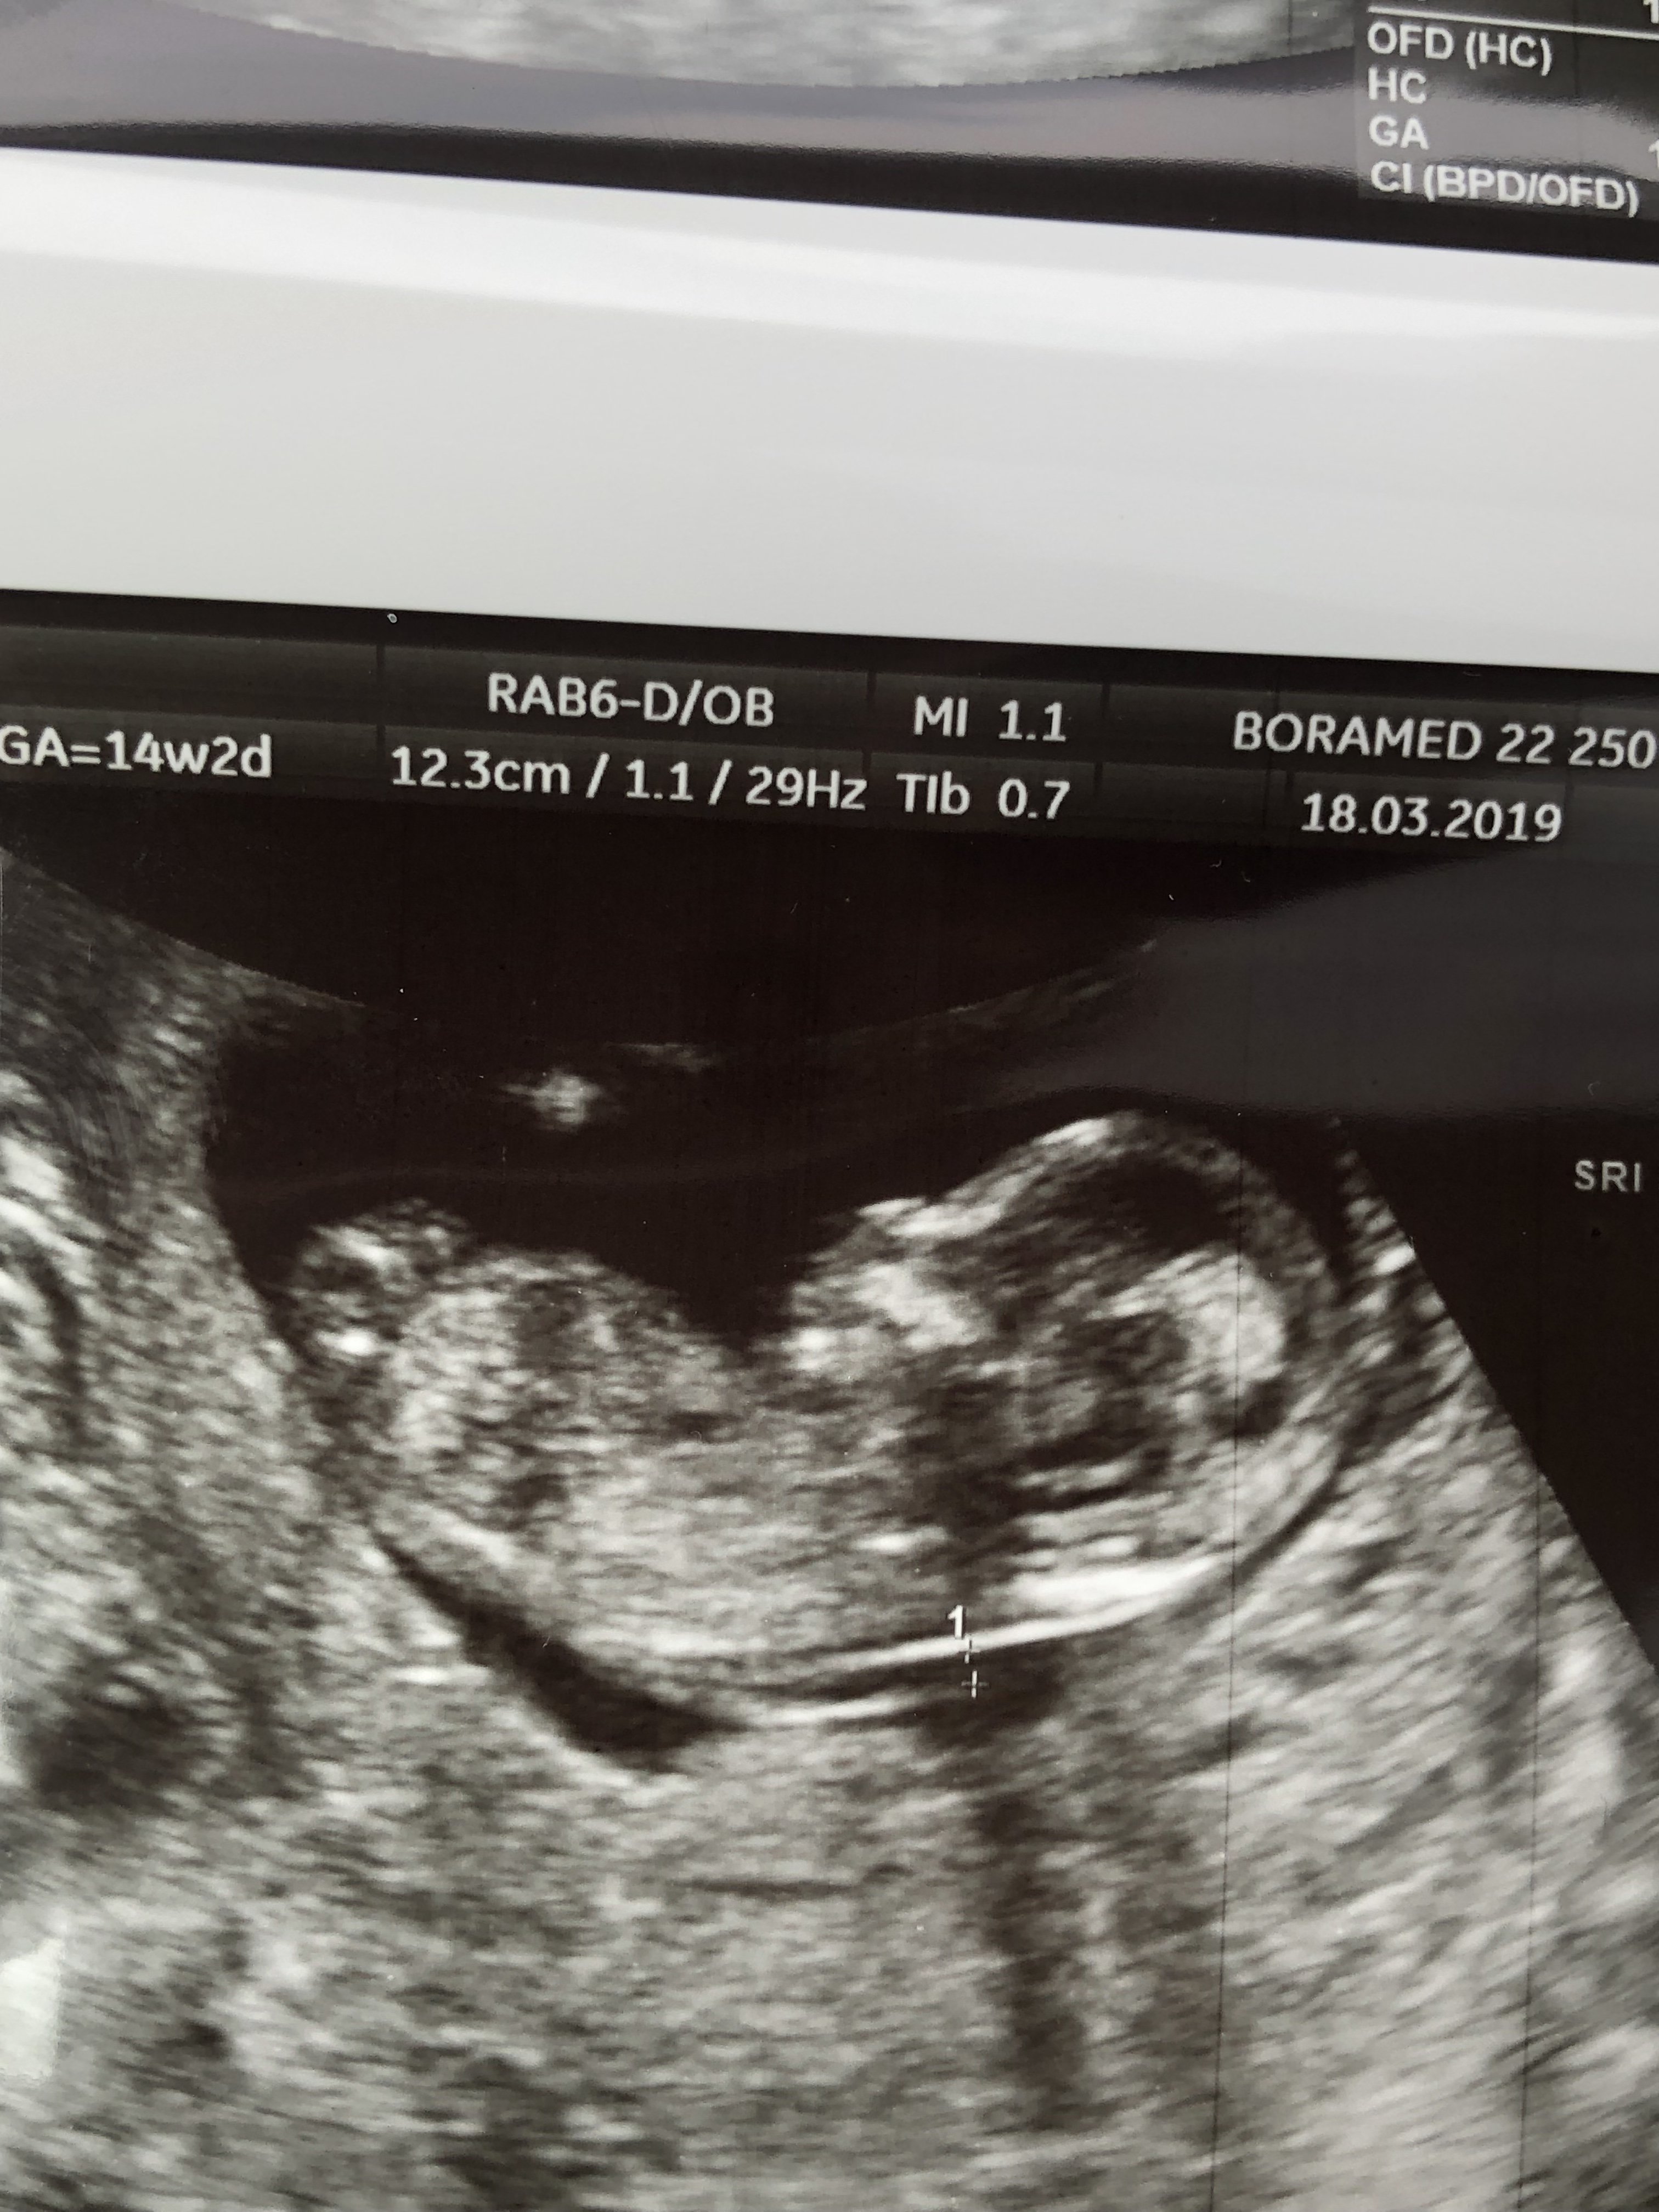

Jeszcze mam coś takiego również z 12+5 ale nie wiem czy coś widać

Pozdr, z góry dziękuje za wszystkie sugestie.

Załączniki

• 3D63C558-5FF5-4B8E-80AB-230D931DE304.jpeg

3D63C558-5FF5-4B8E-80AB-230D931DE304.jpeg

866,3 KB · Wyświetleń: 328

Karmelowe 14tc to już stanowczo za późno na potrzebie z nuba. Teraz idź po 16tc i niech zrobi potty shot.

A tak na serio to nadal masz 50/50 teraz widzę że u ciebie może być stacking ale nie jestem pewna czy widać tam całego nuba. Więc może to też być chlopczyk;)

Z nubami to teraz jest z 60-70% trafień